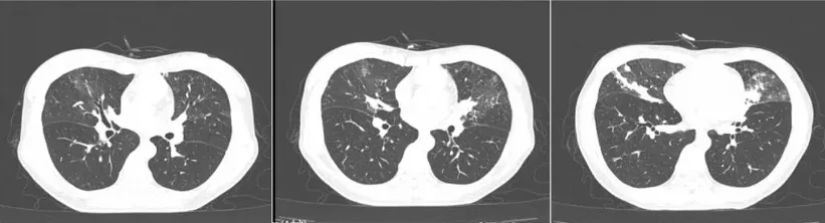

现病史:此次咳嗽咳痰再次出现入院,痰色白,无畏寒发热,无明显胸闷气急,无胸痛咯血等表现。肺CT提示“右肺中叶感染性病变伴部分支气管闭塞,较前(4月前)左肺上叶感染已基本吸收,右肺中叶感染有吸收,两肺散在增殖灶”。支气管镜检查:右肺中叶外侧支痰栓阻塞,开口略狭窄。右肺中叶外侧支肺泡灌洗液送检病原学检查

此次CT: